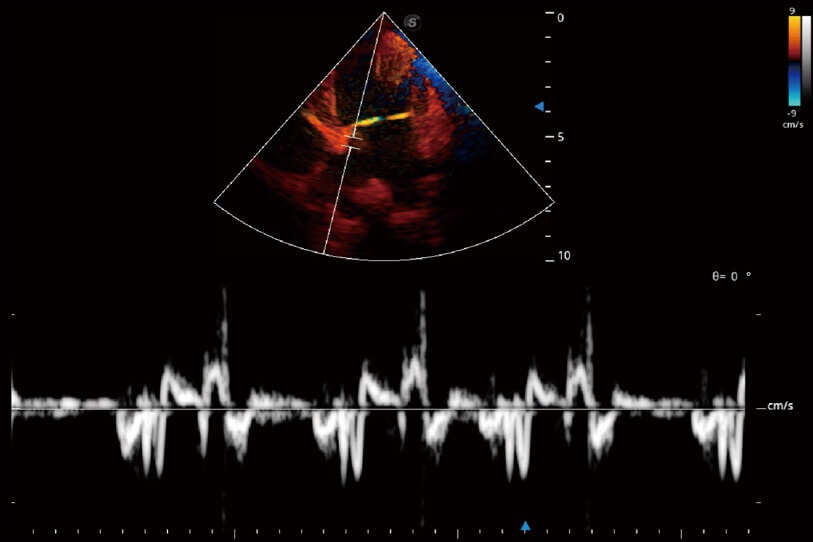

通過(guò)360度任意調(diào)節(jié)3條M型取樣線,在同一心動(dòng)周期上觀察心臟不同位置的運(yùn)動(dòng)曲線,得到準(zhǔn)確的心功能測(cè)量數(shù)據(jù),有效評(píng)估心肌運(yùn)動(dòng)及左心室功能。

實(shí)時(shí)用顏色表示心肌組織運(yùn)動(dòng),觀察和定量組織的運(yùn)動(dòng)情況,對(duì)快速檢測(cè)與評(píng)估心肌的灌注和活性、電傳導(dǎo)及心肌收縮和舒張功能等均能提供重要的診斷信息。